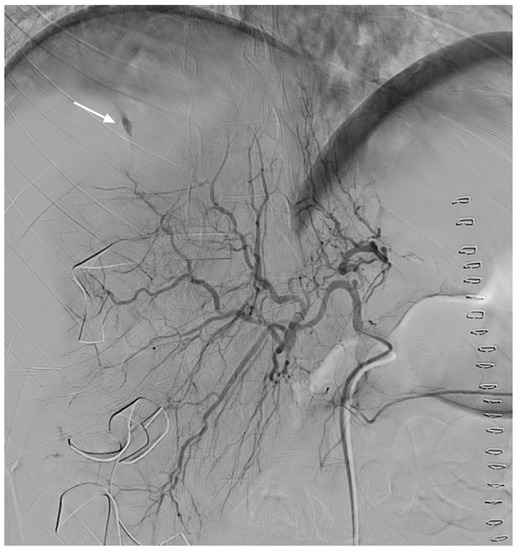

2. Case Presentation